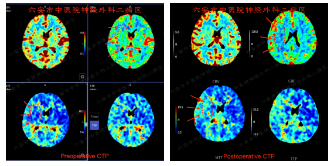

入院后行检查所示

头颅MRI灌注成像提示:右侧局部大脑低灌注表现(左图);术后灌注较前有所改善(右图)。